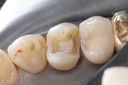

Alan Chinn #28 pre-op